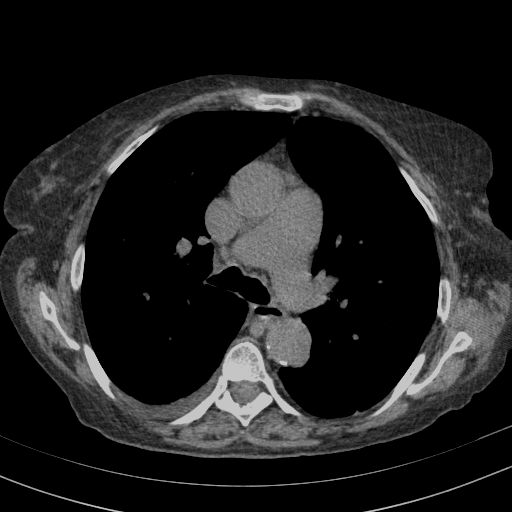

Targeted Slice 70 - Mediastinum Window Analysis (Generated vs Real Venous)

0.629

Mediastinum SSIM

49.0

Mediastinum RMSE

22.4

Mediastinum MAE

Average Mediastinum Window Metrics Across All Slices (153 slices) - Generated vs Real Venous

0.549

Mediastinum SSIM (Avg)

54.0

Mediastinum RMSE (Avg)

28.3

Mediastinum MAE (Avg)

Generated VENOUS CT scan (A→B translation)

Full window (WL 1023.5, WW 4095 β†’ Low βˆ’1024, High +3071)

Mediastinum window (WL 40, WW 400 β†’ Low βˆ’160, High +240)